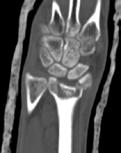

Schatzker III, Osteosinteză cu șuruburi percutană

Schatzker VI, Reducere sângerândă și osteosinteză cu 2 plăci

În fracturile Schatzker I, fără leziuni de menisc extern asociate este indicată reducerea și osteosinteza percutană cu șuruburi. Dacă leziunea de menisc este evidențiată pe RMN, se poate opta pentru reducere și osteosinteză percutană cu șuruburi asociată cu artroscopie(12), având rol de control al reducerii și curativ pentru leziunea de menisc, sau reducere deschisă și fixare internă cu placă și șuruburi.

La pacienții tineri cu fracturi Schatzker tip II și III se poate opta pentru reducere și osteosinteză percutană cu șuruburi asociată cu artroscopie. O altă variantă este cu grefă osoasă și reducere deschisă cu fixare internă cu placă și șuruburi. Controlul reducerii intraoperator se realizează artroscopic sau cu C arm.